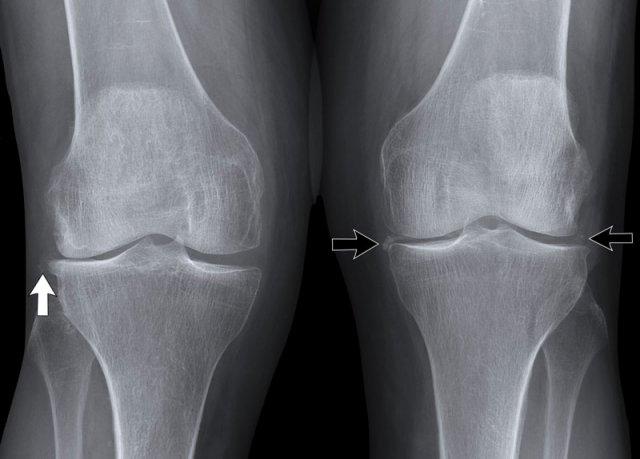

Vôi hóa sụn trong CPPD

Có các vôi hóa mờ nhạt của sụn và sụn chêm ở cả bên phải (mũi tên trắng) lẫn bên trái (mũi tên đen).

Những hình ảnh này có thể do CPPD gây ra, nhưng cũng có thể gặp trong các bệnh lý khác như gút hoặc thoái hóa khớp.

Cũng cần lưu ý hình ảnh hẹp khe khớp và hình thành gai xương mức độ nhẹ.

CPPD có nhiều đặc điểm tương tự thoái hóa khớp.